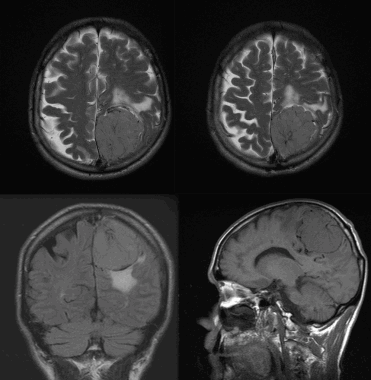

Менингиома теменной области. МР-изображения, полученные с использованием следующих последовательностей: аксиальное Т2-взвешенное, аксиальное Т2-взвешенное, корональное FLAIR -изображение и сагиттальное Т1-изображение. Крупная левосторонняя менингиома выглядит в виде экстрааксиального образования с паттерном «колеса со спицами» и отеком окружающих тканей.

Фалькс-менингиома на МРТ.

А: на Т1-взвешенном МР-изображении отмечается солидное образование, характеризующееся изоинтенсивностью по отношению к твердой мозговой оболочке, инвазией в кость и сдавлением теменных зон коры.

В: На Т1-взвешенном МР-изображении с контрастным усилением видна частично контрастируемая опухоль.

С: На корональном Т2-взвешенном изображении видно изоинтенсивное образование, что соответствует плотной ткани. Такая картина характерна для фибробластных менингиом.

D : На Т1-взвешенном МР-изображении с контрастным усилением визуализируется гиперинтенсивное образование внутри мозгового вещества кости.